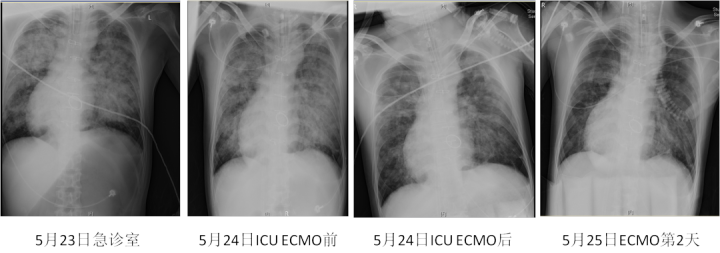

经过医院急诊和ICU的医生会诊评估,决定对小史使用ECMO(体外膜肺氧合)治疗。

张志荣主任说,ECMO治疗是一种高风险的有创治疗,但小史的情况已经到了不得不用的状态。“通俗地讲,小史的肺里呛入了很多水,肺功能已经非常差了。使用ECMO就是用设备暂时取代小史的肺,在保证小史生命体征的情况下,让肺得到休息并进行对症的治疗。”

在上ECMO的第三天,小史的肺部情况持续好转,当天就顺利撤下了ECMO。